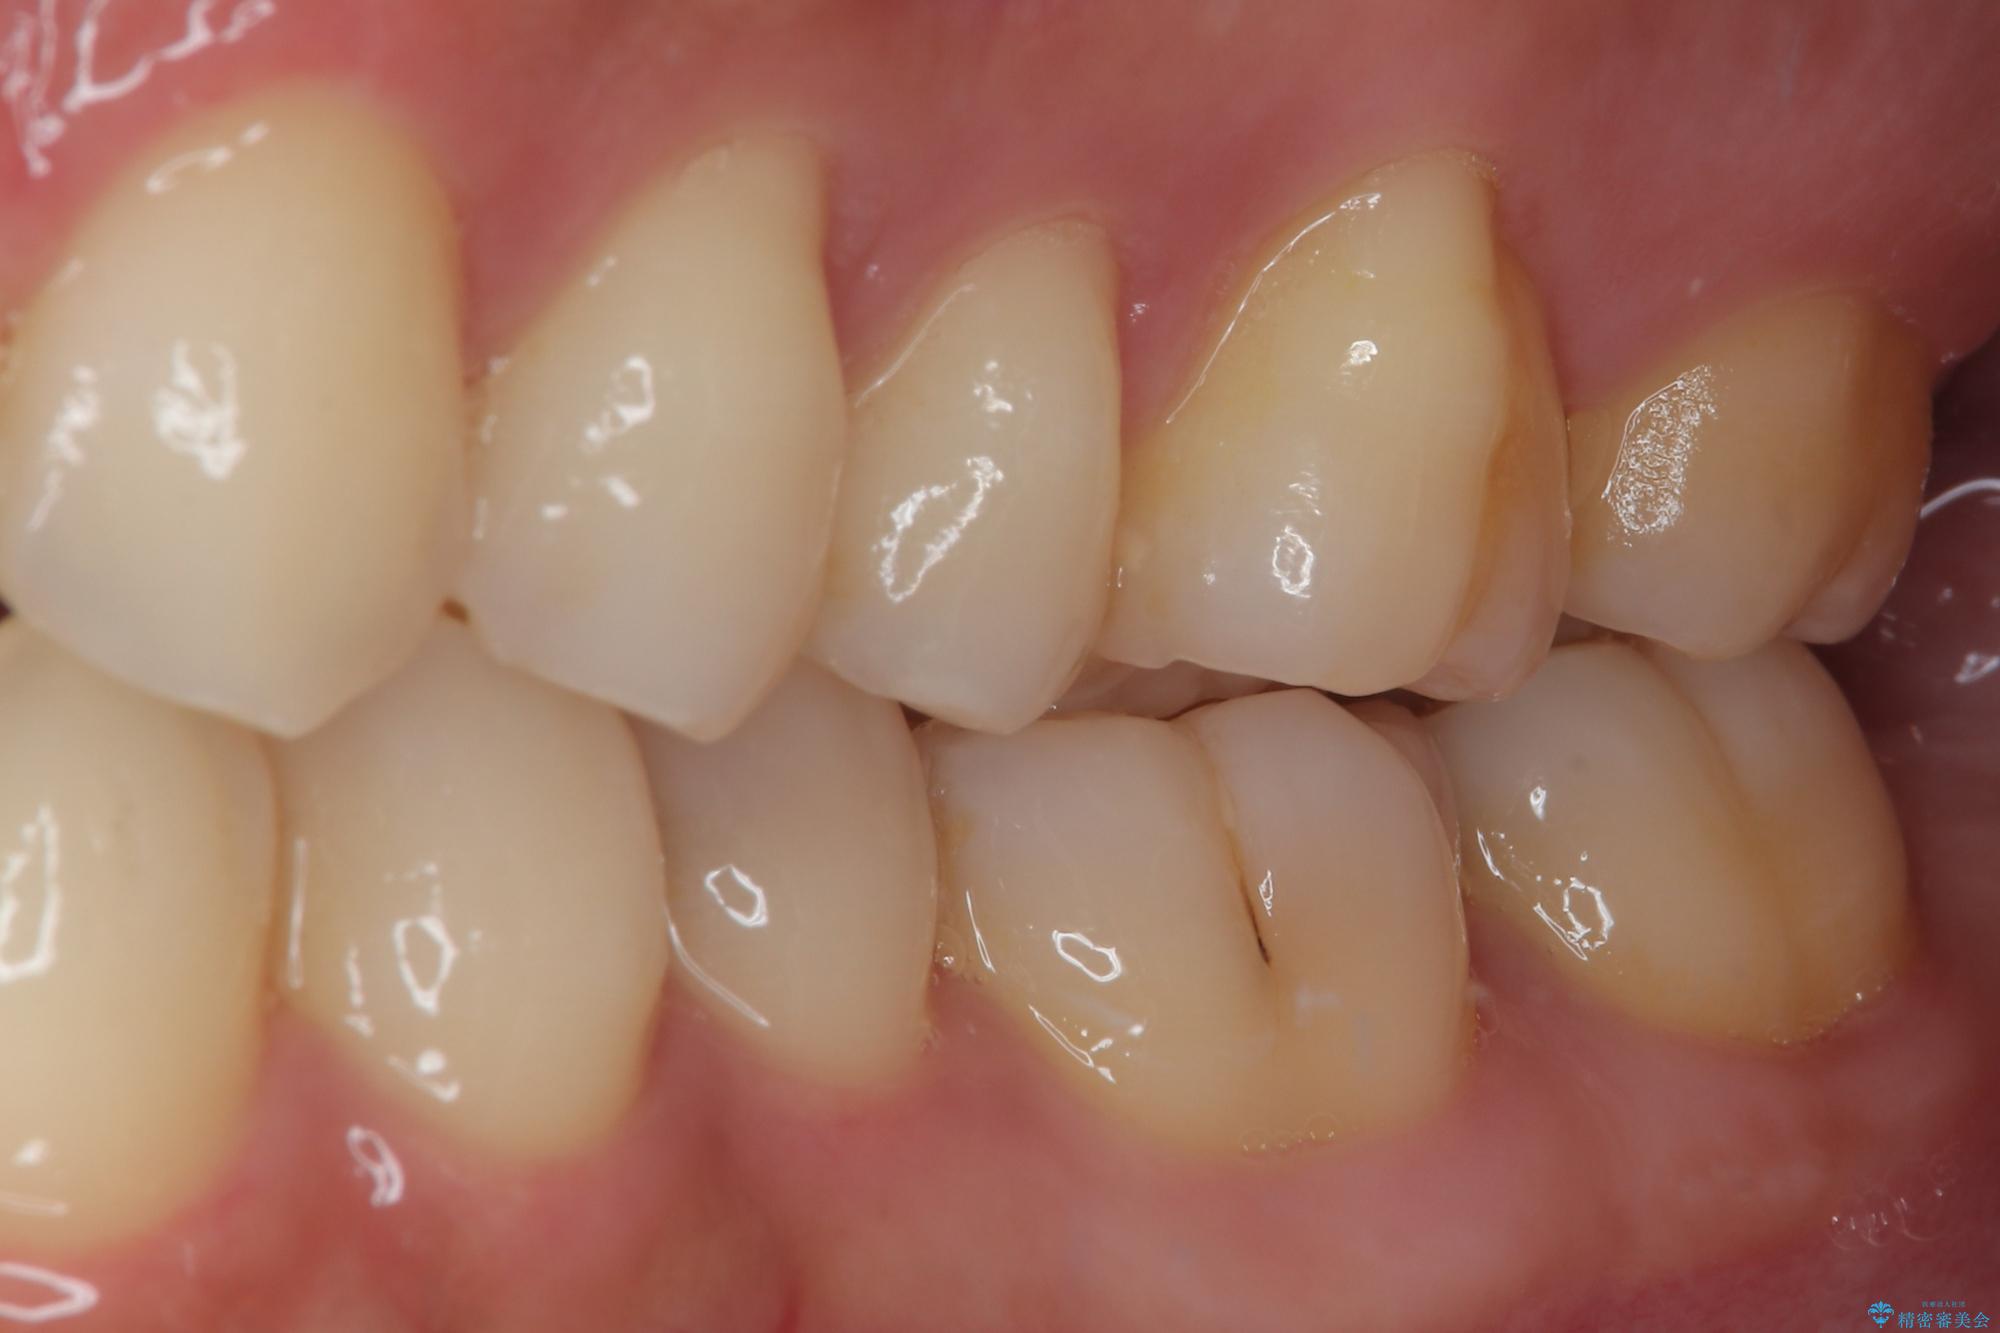

フロスがちぎれることもなくなり、被せものが入っていることを忘れていたと大変喜んでいただきました。適合の良い被せものは二次的な虫歯の再発リスクを低減してくれます。

今後の予定は患者様のタイミングで歯茎から少し見えている親知らず抜歯を行っていく予定です。